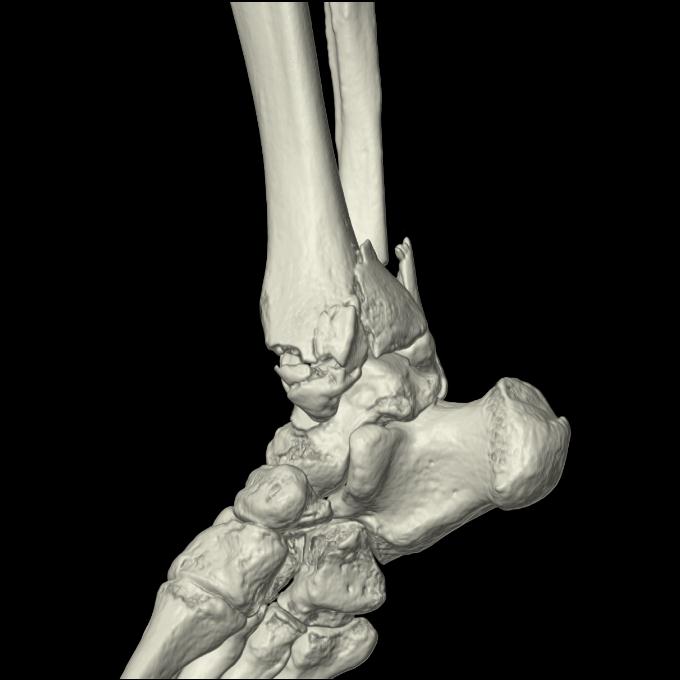

102755 1/4 2R 1/15 2R 右足関節 68歳女性 右三果脱臼骨折